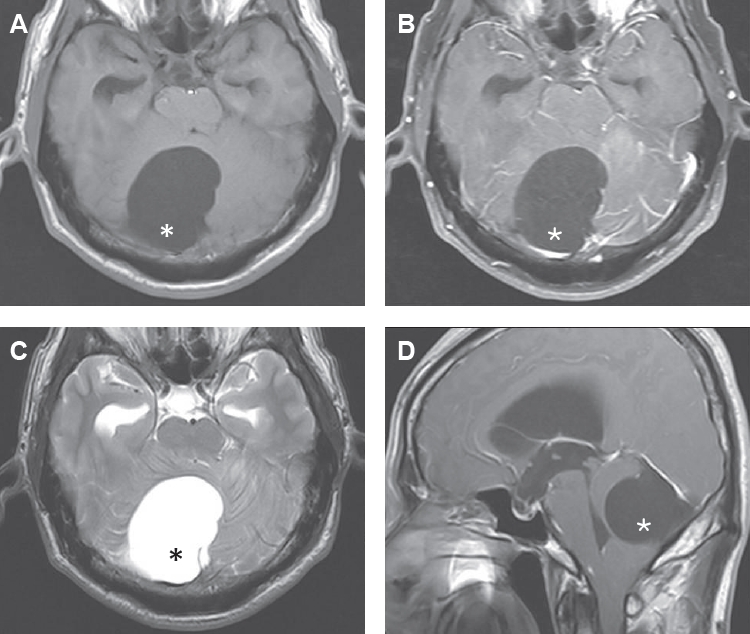

Magnetic resonance imaging (MRI) showed large eccentrically located cyst (6×4.8 cm) within posterior fossa which massively compressed right cerebellar hemisphere and brainstem (

Fig. 1). The cyst was sharply delineated from the cerebellum and compressed the fourth ventricle, resulting in ventricular dilatation (i.e., obstructive hydrocephalus). The cerebellar tonsil was herniated through foramen magnum. The CF exhibited signal intensity identical to that of CSF on MRI, and the cyst wall showed no enhancement on gadolinium-enhanced images. Accordingly, the MRI findings favored a diagnosis of an arachnoid cyst in the posterior fossa. However, the location of the cyst was quite different from that of a typical arachnoid cyst, which is usually located in midline. Because the cyst caused symptomatic hydrocephalus, the patient underwent surgery. Under general endotracheal anesthesia, midline suboccipital craniectomy over the cyst was performed. After incising the dura, thin and transparent cyst wall was exposed freely. Arachnoid membrane was integrated with cyst wall. The authors aspirated cystic fluid using a 23-gauge needle (

3]. In the present study, MRI findings demonstrated that the cyst exhibited signal intensity identical to that of CSF even after gadolinium contrast administration, consistent with previous reports that giant cysts usually have the same signal properties and do not exhibit enhancement after gadolinium administration [

4]. This imaging characteristic is likely attributable to continuous influx of CSF into the cyst. Furthermore, the cyst appeared as a single large cyst without internal septation or conglomeration, and no scolex was identified on macroscopic examination, distinguishing it from the racemose form of NCC.

Fig. 1.Magnetic resonance images show hydrocephalus and a large cyst in the posterior fossa with signal intensity identical to cerebrospinal fluid and no contrast enhancement after Gd-DTPA injection. Asterisks show a large cyst in the posterior fossa. T1 axial image (A), T1 gadolinium enhance image (B), T2 axial image (C), and T1 sagittal image (D).